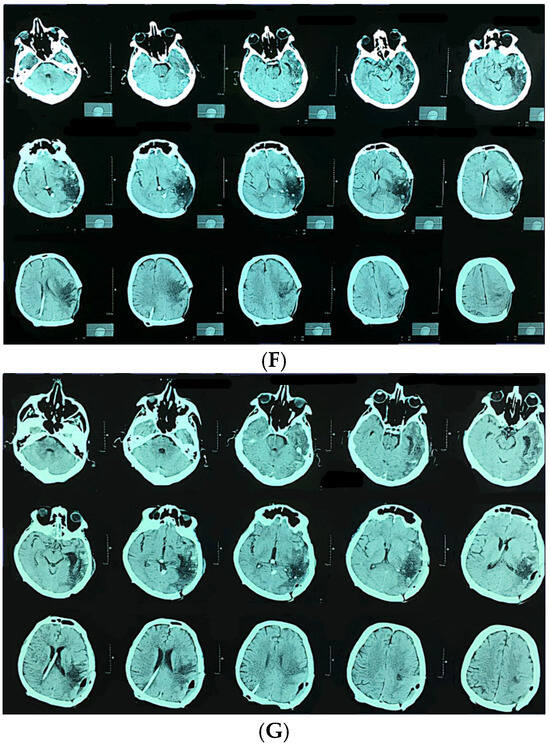

Predictors of Functional Outcome After Microsurgical Resection of Brain Arteriovenous Malformations: A Retrospective Single-Center Study

Background/Objectives: Brain arteriovenous malformations (AVMs) are rare but clinically significant lesions associated with hemorrhage, seizures, and neurological deficits. Microsurgical resection remains the gold standard for low- and intermediate-grade AVMs, though treatment of unruptured AVMs is still debated. To present functional outcomes of microsurgical [...] Read more.

Background/Objectives: Brain arteriovenous malformations (AVMs) are rare but clinically significant lesions associated with hemorrhage, seizures, and neurological deficits. Microsurgical resection remains the gold standard for low- and intermediate-grade AVMs, though treatment of unruptured AVMs is still debated. To present functional outcomes of microsurgical treatment for intracranial AVMs in a high-volume neurosurgical center. Methods: We retrospectively analyzed 111 patients who underwent microsurgical AVM resection between 2010 and 2022 at the Clinical Center of Serbia. Demographic, clinical, radiological, and surgical data were collected. Functional outcomes were assessed using the modified Rankin Scale (mRS) at discharge and after nine months. Results: The mean patient age was 36 years (range 8–75); 54 (48.6%) were male. AVMs were most often supratentorial (91.9%), located in the frontal (26.1%) and temporal lobes (19.8%). Hemorrhage was the presenting symptom in 53.2% of patients. Postoperative complications included hematoma (10.8%), meningitis (13.5%), and wound infection (8.1%). The mean mRS at discharge was 2.10, improving significantly to 1.15 at nine months (p < 0.001). Favorable outcome (mRS ≤ 2) was achieved in 64.0% at discharge and 81.1% at nine months. Prognostic factors for poor outcome included AVM size larger than 6 cm, higher supplementary Spetzler–Martin grade, and combined venous drainage. Conclusions: Microsurgical resection provides an important component of multidisciplinary AVM management, especially in low- and selected intermediate-grade lesions, achieving favorable functional outcomes in the majority of patients. Careful patient selection, AVM grading, and venous drainage analysis remain essential for prognosis and treatment planning. Full article